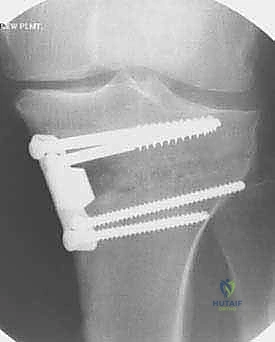

باستخدام أدوات دقيقة ومناشير جراحية متطورة، يتم عمل قطع غير مكتمل في عظمة الساق. هناك طريقتان رئيسيتان:

* الشق المفتوح (Opening Wedge): يتم فتح العظم من الداخل وإضافة طعم عظمي (صناعي أو طبيعي) لملء الفراغ وتعديل الزاوية. وهي الطريقة الأكثر شيوعاً حالياً.

4. تعديل المحور:

يتم فتح العظم تدريجياً وببطء شديد حتى الوصول إلى الزاوية التي تم حسابها في التخطيط الرقمي قبل الجراحة.